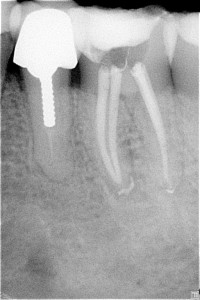

Fallbeispiel-2_Bild_3_Pat_781_Za_36_R__ntgenkontrolle_n_WF Posted on 5. Februar 201615. Februar 2016 by Administrator